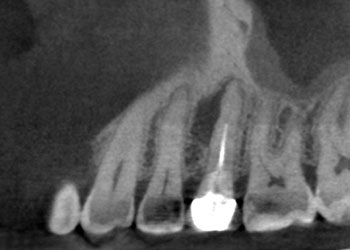

Case 1:A J-shaped lesion

Tooth #30 had a diagnosis of previous root canal treatment with symptomatic apical periodontitis. The mesial root had a classic J-shaped radiographic lesion and a narrow probing defect from the buccal furcation to the root apex. No crack could be seen on what little root surface was visible. The likelihood of VRF, or the possibility of a failing root canal with a chronic apical abscess, were discussed. The latter could be treatable. The plan was to attempt re-treatment after internal inspection for a possible VRF.

Fig. 1: Preoperative PA.